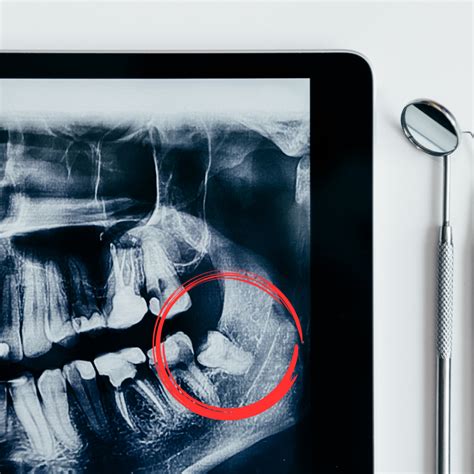

- Mala posición: Su posición inclinada o torcida en la boca puede provocar que queden atrapadas y no puedan salir del todo, lo que puede provocar inflamación, malestar al comer y dolor al hacer presión sobre los otros dientes.

En otros casos, las muelas del juicio pueden salir con una inclinación horizontal, apiñándose con dientes cercanos, a los que pueden acabar dañando. A veces, la vía de erupción de las muelas del juicio es correcta, pero si los maxilares no tienen suficiente espacio para albergarlas puede que no lleguen a emerger, y queden retenidas en la mandíbula.